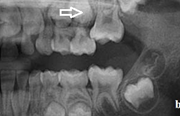

Esimeste molaaride (purihammaste) lõikumine

Esimeste molaaride (purihammaste) lõikumine. 1. molaaride ektoopilise lõikumise jälgimine. Ülemised ja alumised esimesed purihambad e. molaarid lõikuvad orienteeruvalt6-7-aastaselt piimahammaste rea lõppu. Enamasti lõikuvad samanimelised jäävhambad paaridena. Normaalne lõikumise Loe edasi »